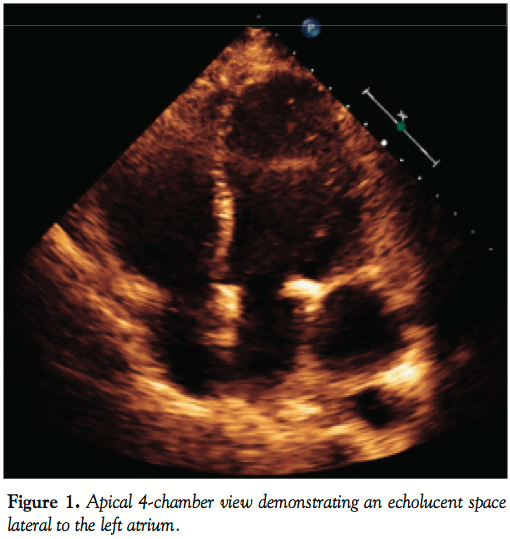

patent bypass grafts and normal pressures on right heart catheterization. Chest CT showed a poorly defined aneurysm in the left side of the heart. Transthoracic and transesophageal echocardiograms revealed a 5 cm LV pseudoaneurysm (Figures 1 and 2). Cardiac MRI showed a 4.2 x 4.3 x 5.8 cm cavitary lesion adjacent to the posterolateral wall of the left ventricle and a small tract from the LV cavity to the cavity (Figure 3). Flow turbulence was noted across this tract. She was referred to cardiothoracic surgery for surgical repair of the pseudoaneurysm. Given the patient’s comorbidities including significant recurrent problems with wound healing, and after careful discussions of risks, benefits, and alternatives, we referred the patient for percutaneous closure of the pseudoaneurysm.